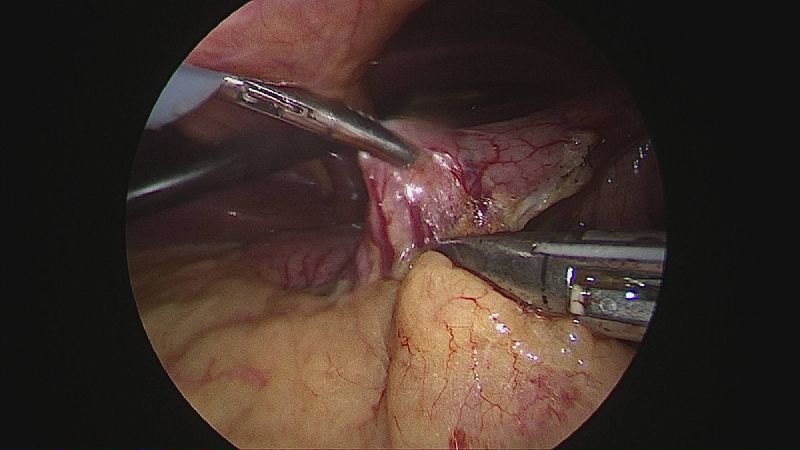

Gastrectomia longitudinală (gastric sleeve) este o intervenție care produce scăderea în greutate prin două mecanisme: restrictiv (îndepărtează o mare parte din stomac lăsând un rezervor de 80-120 ml) și hormonal (prin extirparea fundului gastric se reduce semnificativ secreția hormonului foamei, grelina).

Operația ”de micșorare a stomacului” se realizează miniminvaziv (laparoscopic) și constă în îndepărtarea marii curburi gastrice cu păstrarea antrului gastric și a micii curburi sub forma unui tub calibrat pe o sondă.

Tehnica aduce beneficiile chirurgiei laparoscopice, durere redusă, externare în primele 48 ore de la intervenție. Avantajul său constă în confortul oferit pacientului care prezintă senzația de sațietate rapid prin umplerea unui stomac de doar 100 ml, reducerea senzației de foame prin suprimarea secreției de grelina. De asemenea, nu modifică traseul alimentelor, nu exclude segmente digestive din circuit și pierderea excesului ponderal poate ajunge până la 100%.